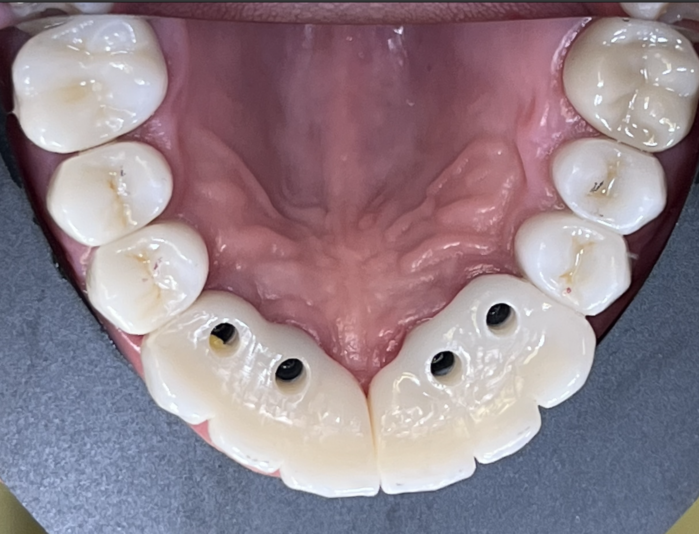

Hi everyone. I am new to placing implants and have been planning some cases and a couple have made me question what the proper plan should be.

Case #1 patient has limited mesiodistal space. Nearing 6mm. It is #5 location. My main concern is obviously lack on space but also what size implant is appropriate for certain teeth. This area has…

Appreciate the reply and information! Looking at the mental it doesn’t seem like it issue but when you see exit on the buccal side it looked like the 10.5mm got a little close. But that’s all great info. Thank you